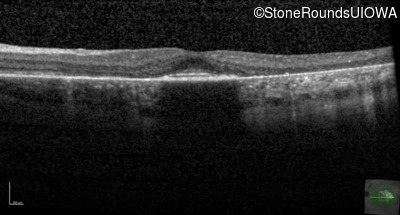

Age at visit: 30 years

This 30 year old man first noticed poor vision in dim light when he was five years old. His visual acuity began to fall in his early 20's.